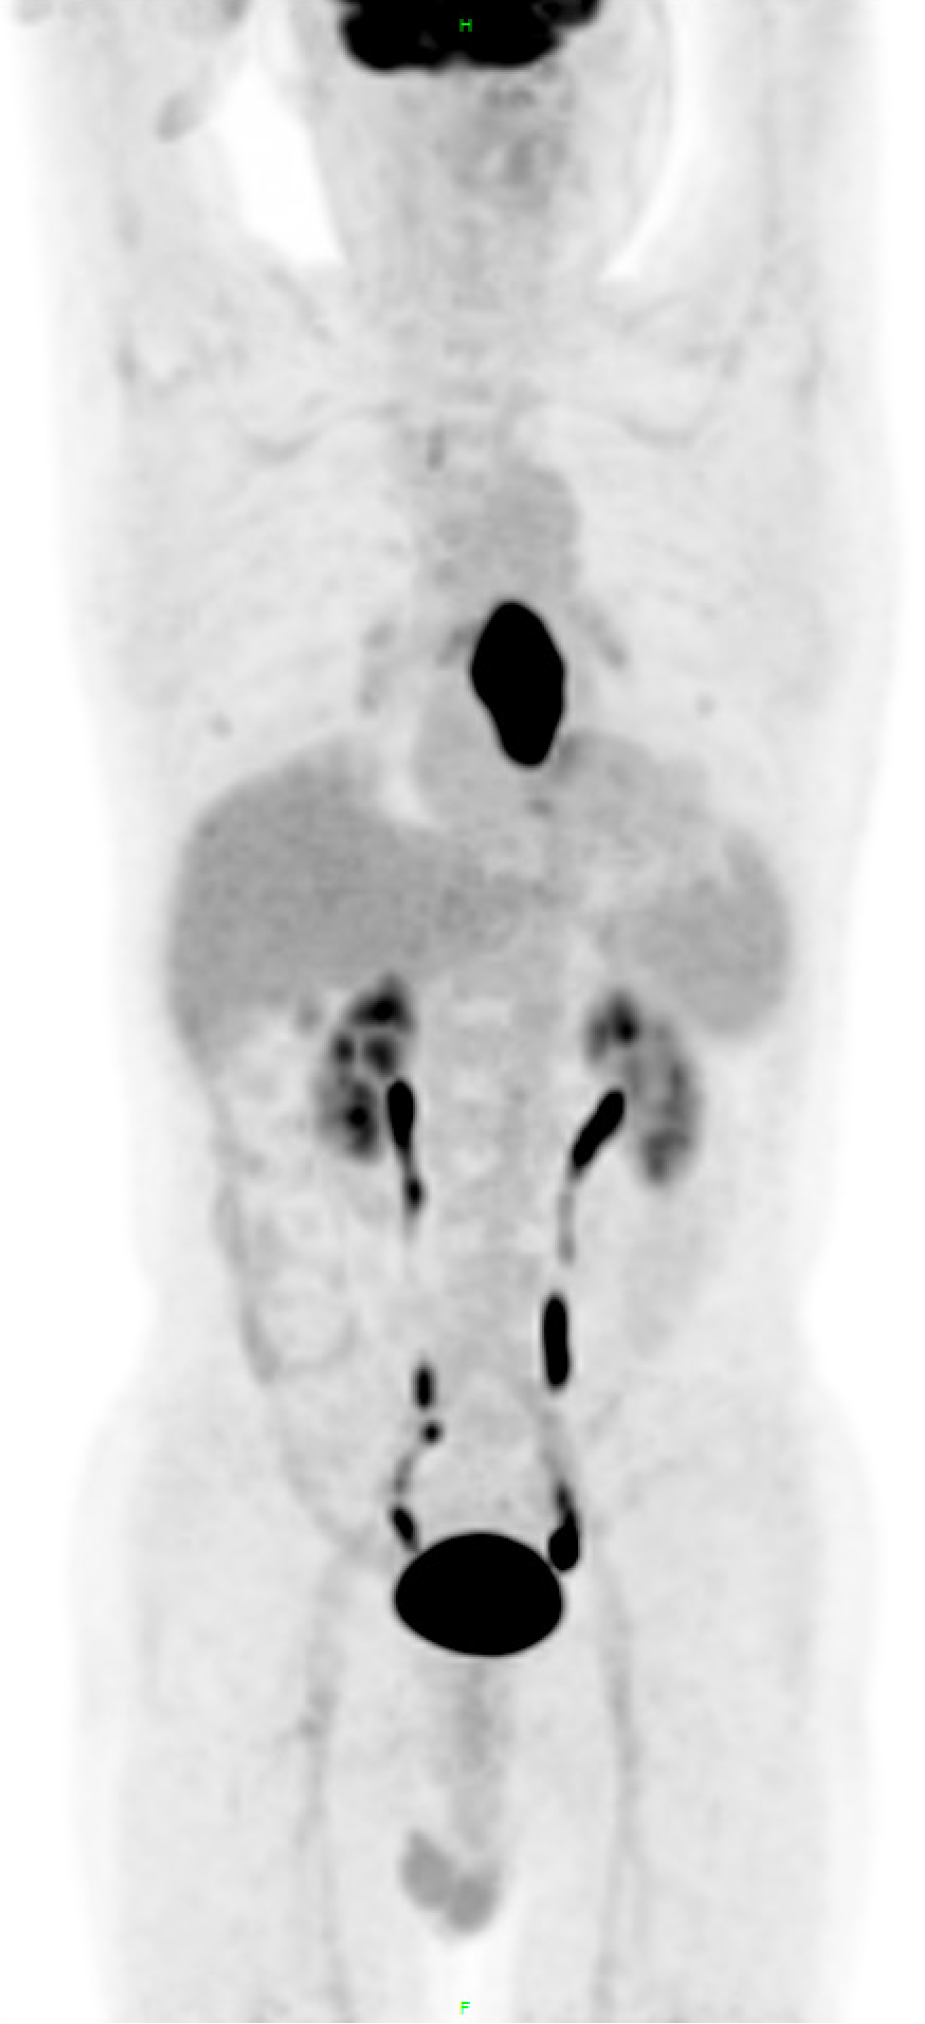

Figure 2

Whole-body absorption graph.